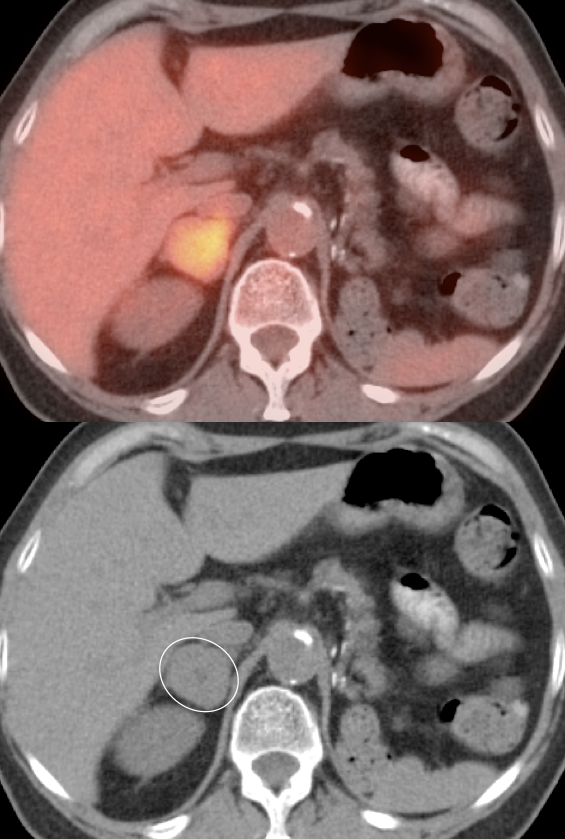

Primary Lesion:  Because many primary RCCA lesions are only mildly FDG avid, we must raise a suspicion of RCCA for any FDG-avid renal lesion (cystic or solid) — unless we can clearly characterize it as a fat-containing angiomyelolipoma.

• On occasion, an incidental RCCA will be identified.

Common: Pooling of FDG-avid urine in a renal calyx.